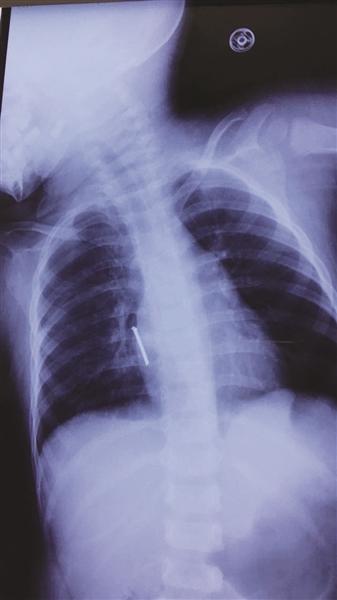

胸片显示,气钉扎进孩子胸腔,差一点就要了孩子的命。胸片显示,气钉扎进孩子胸腔,差一点就要了孩子的命。

一瞬间,一个长5厘米左右的钉子射进阳阳的心脏附近!据了解,气钉枪打出钉的力度很大,很有冲击力和杀伤力,速度一般60米/秒,厉害的可射穿1cm钢板。许先生看到此景,整个人都蒙了。带阳阳火速去医院,他在心里不停祈祷:“千万别刺到心脏!千万别……”

钉尖穿入右心房肌层3毫米

“从片子上看,钉子尖就靠近心脏。如果直接拔钉子,钉子穿透心脏的话,会引起大出血,继而危及生命,也可能胸腔内存有大量积血会填塞心脏,十分危险。”

在进行充分评估后,专家们决定手术打开胸腔,后发现钉子的钉尖已经穿入右心房肌层3毫米,已造成胸腔积血150毫升。“如果钉子再深入一点,那抢救都来不及了。”所幸手术顺利,阳阳脱离了生命危险。